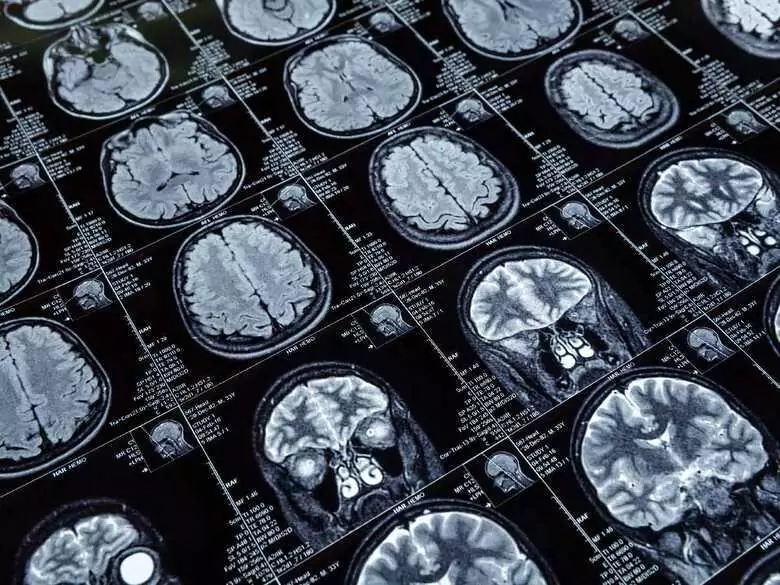

Zakrzepica zatok żylnych mózgu jest stosunkowo rzadko występującym schorzeniem, które zaliczane jest do tzw. udarów żylnych. Stanowi do około 1% wszystkich udarów. Najnowsze badania naukowe potwierdzają, iż problem ten częściej dotyka kobiety aniżeli mężczyzn. Objawy zakrzepicy są bardzo niespecyficzne, co prowadzi do problemów z jednoznacznym i szybkim rozpoznaniem choroby. Co powinniśmy wiedzieć o zakrzepicy zatok żylnych?